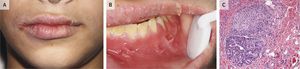

A 13-year-old boy presented with a 9-month history of episodic unilateral swelling of the face and oral pain. He reported having loose, nonbloody stools. Physical examination revealed asymmetric swelling of the face and lips with perpendicular fissuring (Panel A), and intraoral examination revealed discrete gingival erythematous hyperplasia and epulis fissuratumβlike soft-tissue tags in the mucobuccal fold (Panel B). Granulomatous inflammation consistent with Crohnβs disease was found on histopathological examination (Panel C), and the patient was referred to a pediatric gastroenterologist. He was found to have tenderness to palpation in the right lower quadrant and periumbilical region, a rectal fissure, and painless rectal skin tags. Colonic biopsies showed chronic active colitis that was most prominent in the cecum and ascending colon, which confirmed a diagnosis of Crohnβs disease. Therapy with mesalamine and prednisone was initiated and slowly tapered. Maintenance of remission was achieved with mercaptopurine. The oral lesions slowly resolved over a 1-year period. At a follow-up visit 2 years after the initial presentation, the patient remained asymptomatic.